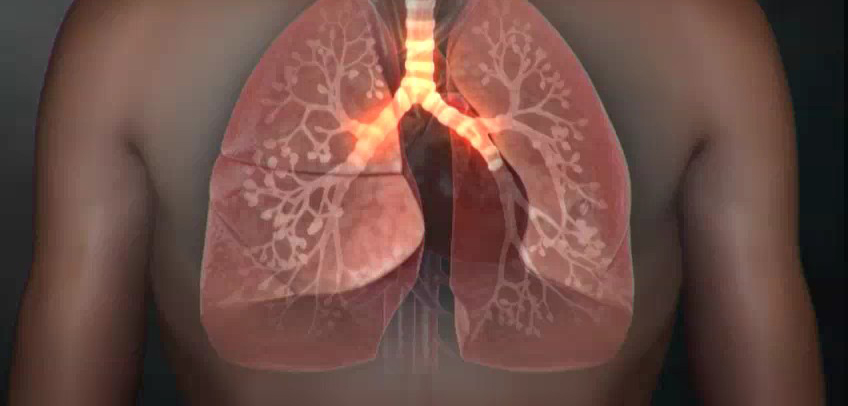

3. 호흡곤란

- 폐에 염증이 생겨 산소 교환이 제대로 안 되면 숨이 차고 호흡이 가빠짐

- 계단을 오르거나 조금만 움직여도 숨이 찰 수 있음

- 심하면 휴식 중에도 숨쉬기가 힘들어지고 청색증(입술, 손끝이 파래짐) 발생